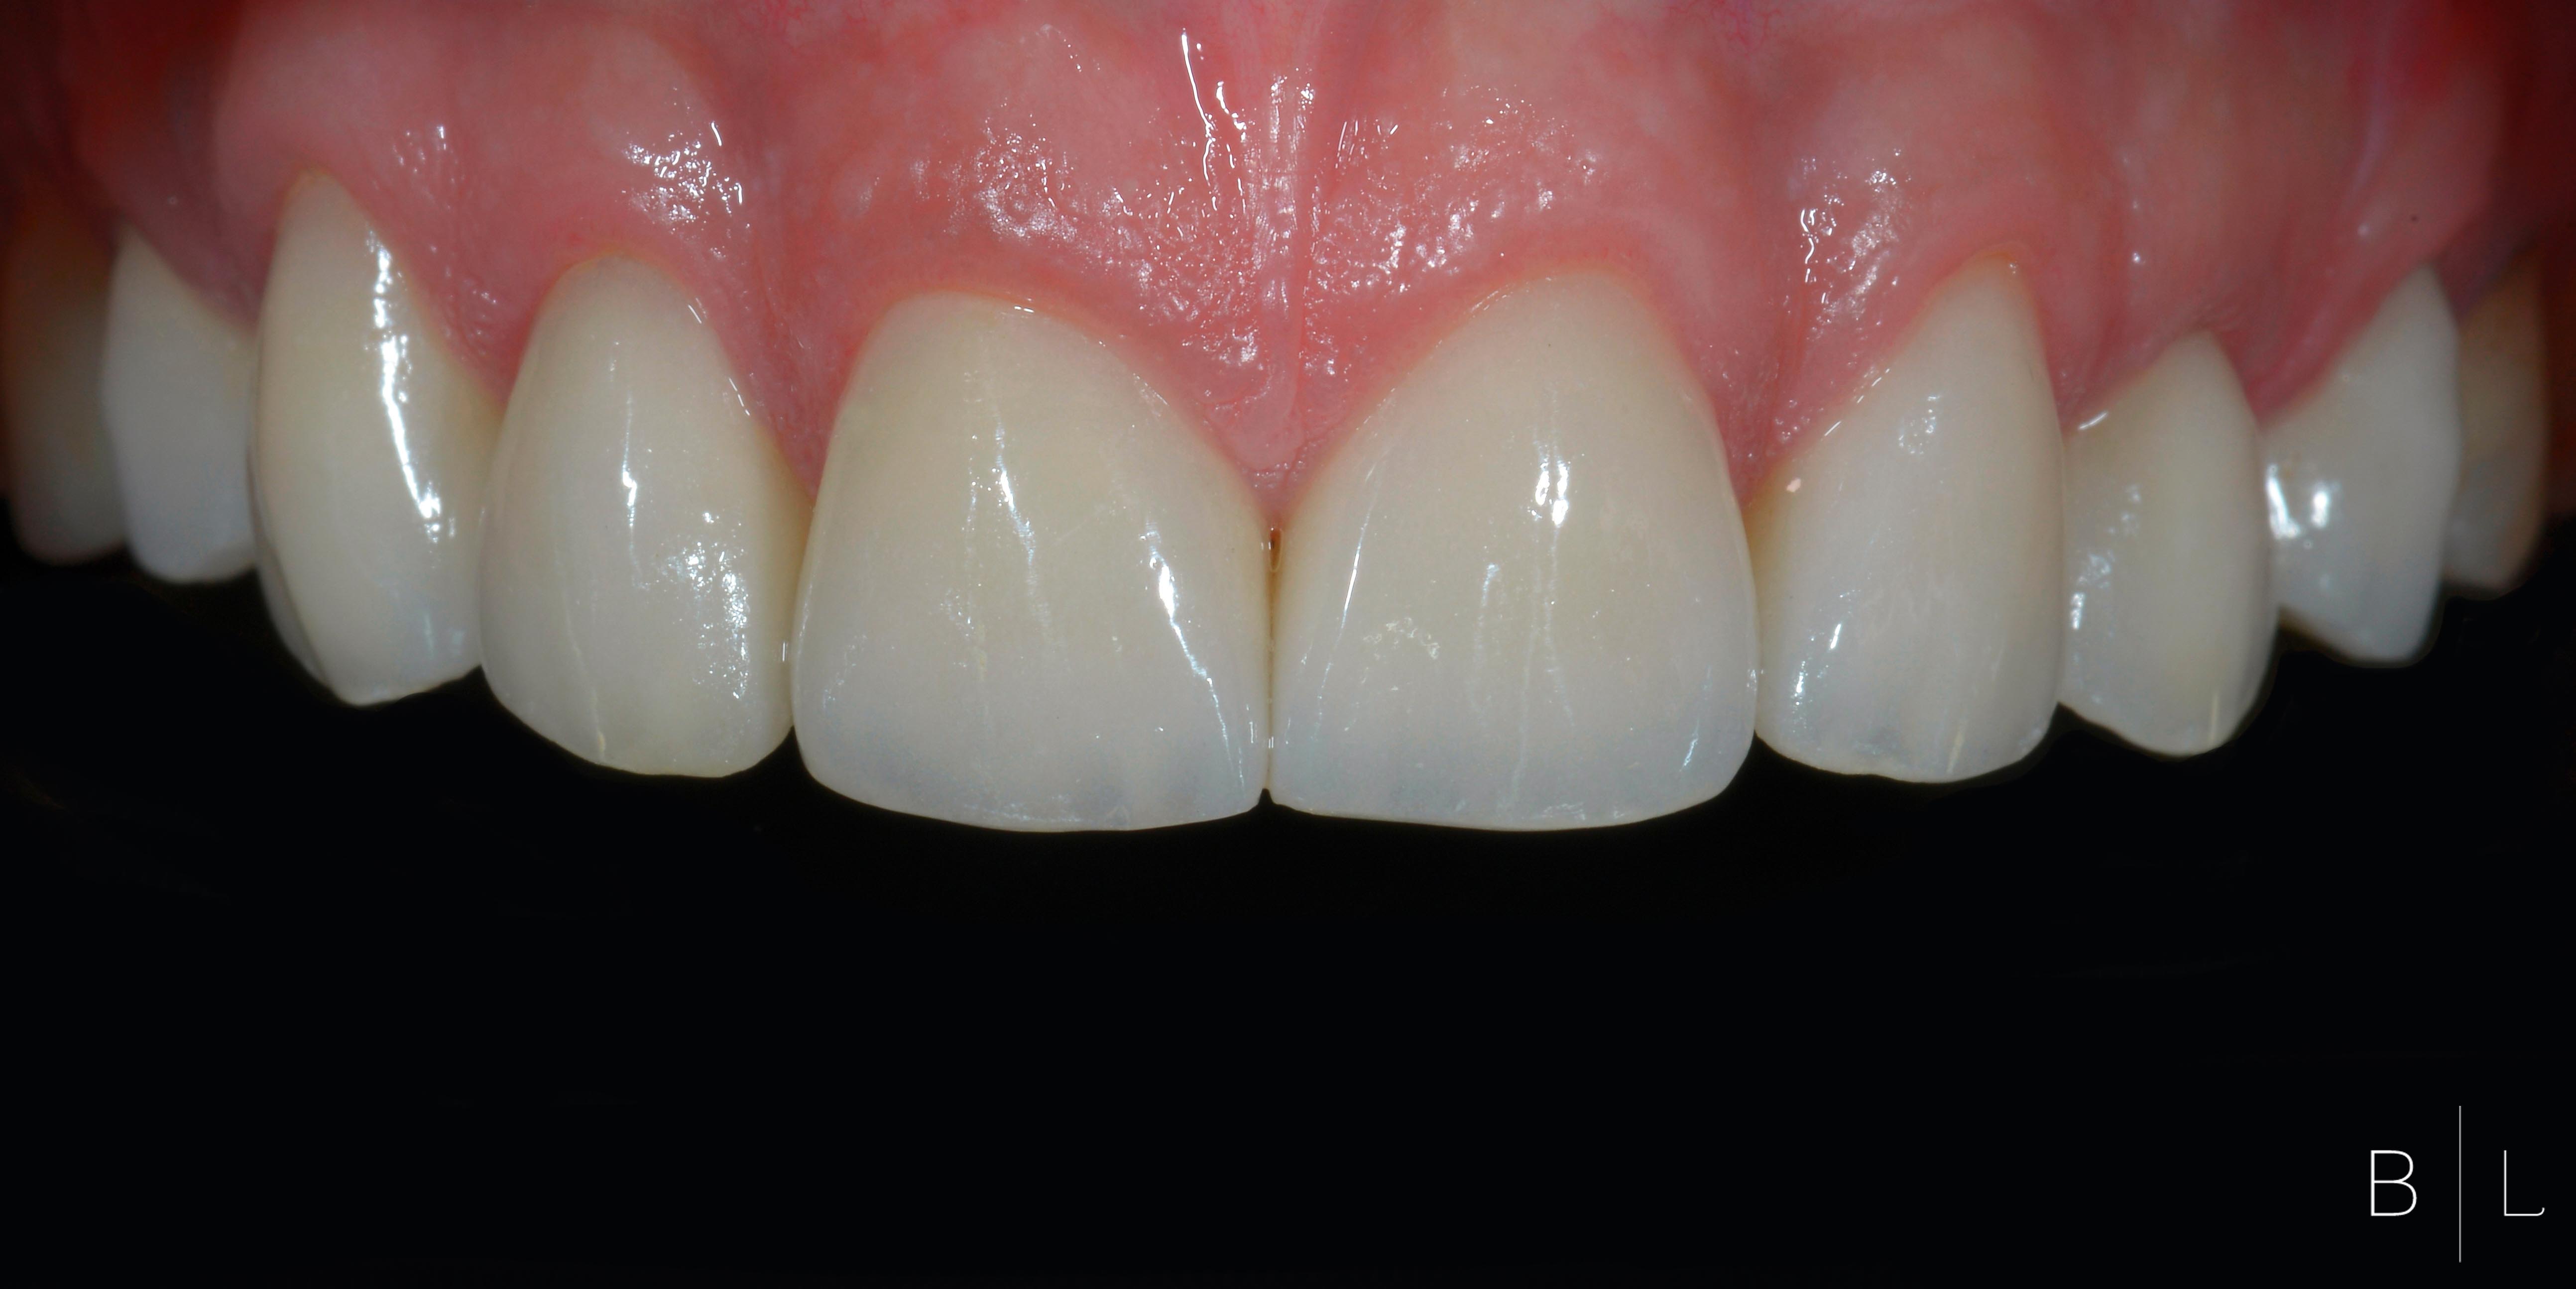

Gum Power! La gencive adore la céramique! Team Prothesia.

Gum Power! La gencive adore la céramique! Team Prothesia.